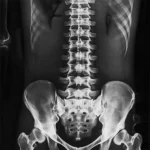

X-ray remains the most widely used diagnostic imaging modality worldwide. In Dubai, it serves as the essential first-line investigation for a broad range of clinical concerns, from sports injuries and workplace accidents to chronic conditions like osteoarthritis and scoliosis. Our digital radiography system captures high-resolution images that allow radiologists to detect subtle findings that older film-based equipment might miss.

Scoliosis & Spinal Alignment

Full-spine X-ray is the standard imaging tool for measuring spinal curvature, monitoring progression in adolescents, and planning treatment strategies.